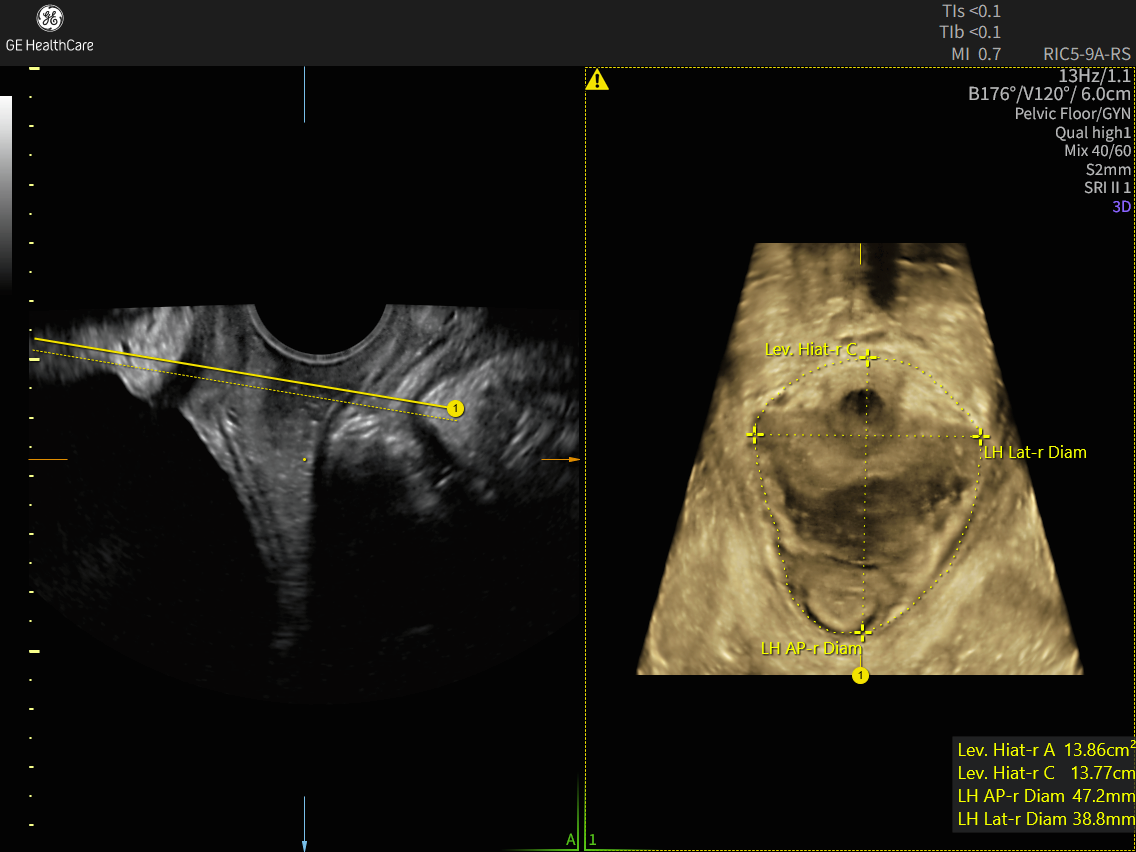

Simplify and speed up pelvic floor exams with automated plane alignment and automated measurements for more consistent, reproducible results, and can reduces pelvic floor exam time by up to 75%.